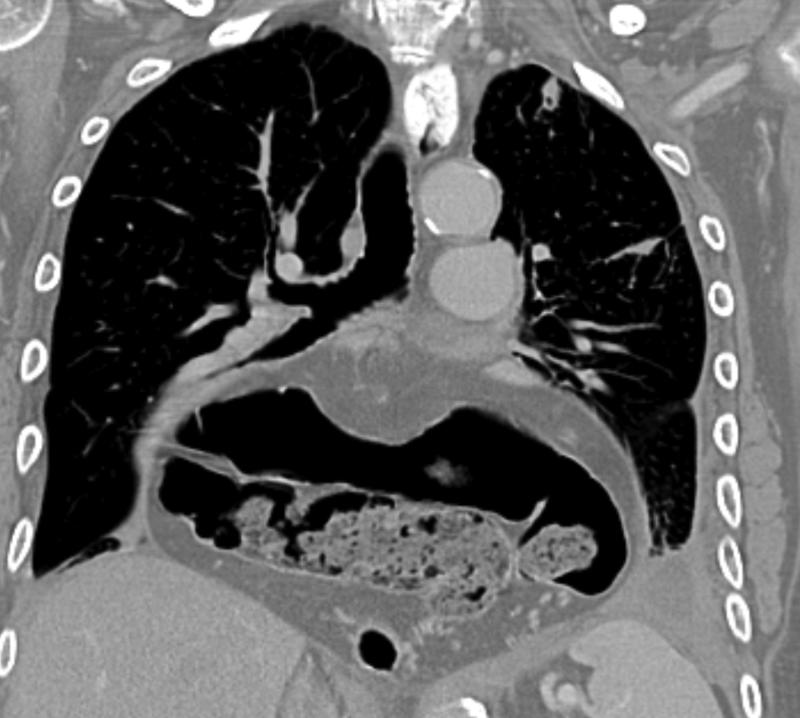

Gallery Mediastinum Hiatus Hernia Hiatus hernia containing stomach and transverse colon

Hiatus hernia containing

stomach and transverse colon